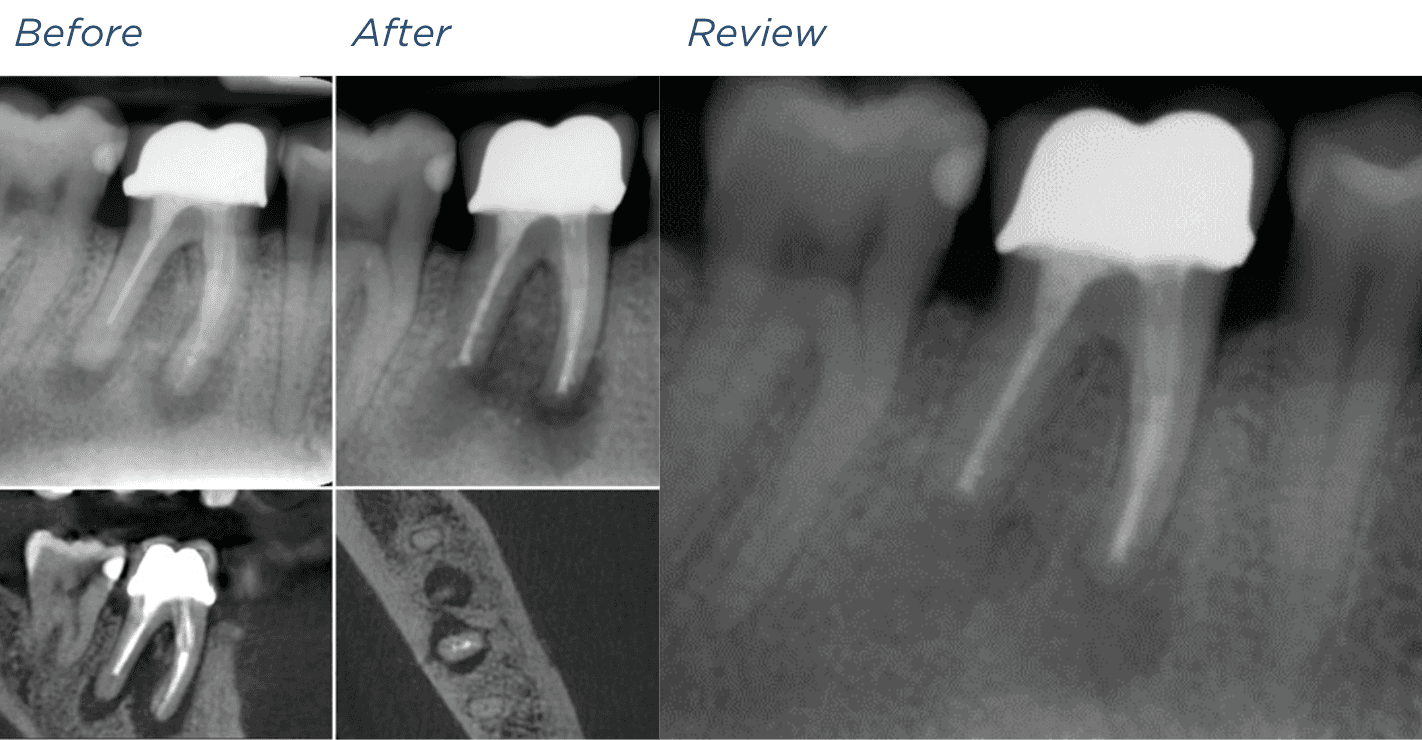

A CBCT (cone beam CT) scan provides a detailed 3D image of your tooth and surrounding bone. It allows us to assess hidden canals, fractures, infection, or bone loss that are not always visible on regular X-rays.

This advanced imaging is especially helpful in complex or previously treated teeth, giving us the most accurate picture for diagnosis and treatment planning.

KREENA'S CASES